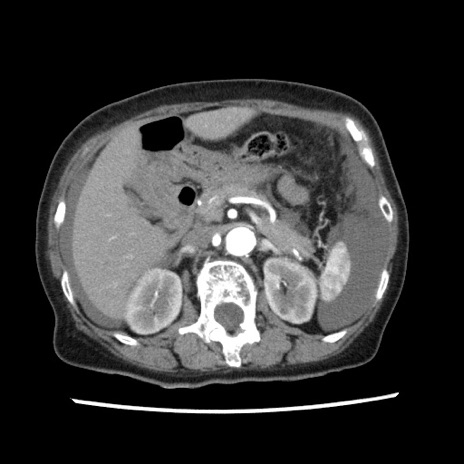

冠状断像

【症例】80歳代女性

【主訴】腹痛

【現病歴】8時間前から腹痛あり来院。

【既往歴】糖尿病、脂質異常症、子宮体癌にて子宮全摘術

【身体所見】意識清明・会話良好だが腹痛で苦悶様、全腹部にわたって反跳痛と圧痛あり

【データ】WBC 13600、CRP 0.14、LDH 224、CK 90